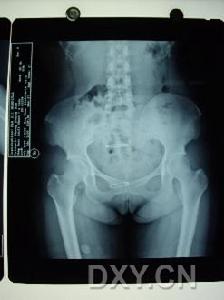

检查时在站立位脊柱前弯、后伸及侧弯均受限,并有局部疼痛,但坐位时活动较好。卧位直腿抬高试验,患侧受限并有局部疼痛。压挤或分离髂骨时患部疼痛,骶髂关节患部有压痛,可有寒性脓肿或窦道。肛指检查有时可摸到局部脓肿及压痛。X线照片检查对早期诊断很重要,需照骶髂关节正位及斜位(关节的矢状面),可见骨质破坏、死骨及空洞形成等。

主要根据其临床表现和辅助检查的结果,主要是X线检查。检查时在站立位脊柱前弯、后伸及侧弯均受限,并有局部疼痛,但坐位时活动较好。卧位直腿抬高试验,患侧受限并有局部疼痛。压挤或分离髂骨时患部疼痛,骶髂关节患部有压痛,可有寒性脓肿或窦道。本病的辅助检查方法主要依靠X线和CT检查,其表现主要有以下几个方面: 医学百科网 | YxBaike.Com

1、病变部位:骨型关节结核主要在骶髂关节前下1/3髂骨松质部。滑膜结核也可穿破关节软骨而侵入骨组织,引起骶髂关节面及骨组织破坏。

2、骨质破坏:骨型关节结核骨破坏区呈圆形或椭圆形,破坏区边缘可见,骶髂关节间隙无明显狭窄。滑膜型关节结核表现为骶髂关节面不同程度的模糊或糜烂,其间隙不同程度的狭窄或增宽;有的显示骨质明显破坏,关节间隙不规则增宽。 医学百科网 | YxBaike.Com

骶髂关节结核--病变部位3、死骨:有学者认为结核可以出现大块死骨,有资料显示结核最大死骨长径可达2cm以上,关于细小颗粒状或“砂粒样”死骨,可能是干酪物质的钙化点,也可能是真正的“砂粒样”死骨。真正的“砂粒样”死骨密度要比上述钙化点低,而且常为钙化的干酪物质所掩盖,故此,二者有时难以区别或显示。

4、骨质增生硬化:骶髂关节结核无瘘管形成,未发生继发感染亦可出现骨质增生硬化,其原因在于骶髂关节结核的骨质疏松常不如其他关节明显,而往往显示有骨质增生硬化征象。

5、冷脓肿和窦道形成:骶髂关节结核较易发生冷性脓肿和窦道形成,多发生在臀部及腹股沟或骨盆内。 医学百科网 | YxBaike.Com

X线摄片早期关节面模糊,边缘糜烂,关节间隙增宽,晚期关节间隙变窄。并有窦道,常继发感染。关节呈现硬化。关节破坏严重者同侧髂骨和耻骨可上移发生病理脱位。